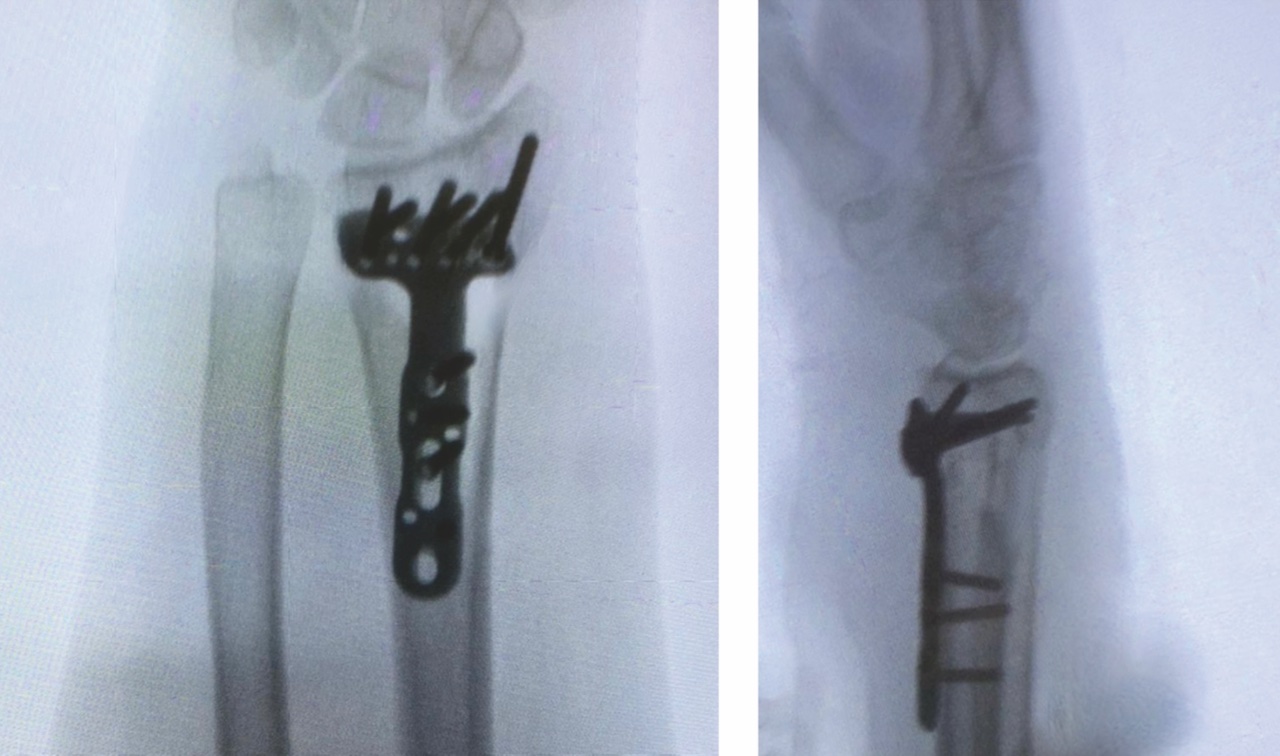

La maggior parte delle ricerche sull’osteosintesi interna evidenzia una superiorità delle placche volari nei confronti delle placche dorsali per ragioni sia biomeccaniche che biologiche. La via di accesso chirurgica di Henry è infatti rispettosa nei confronti dei tendini estrinseci e preserva meglio il supporto vascolare della metafisi del radio distale (Fig. 1).